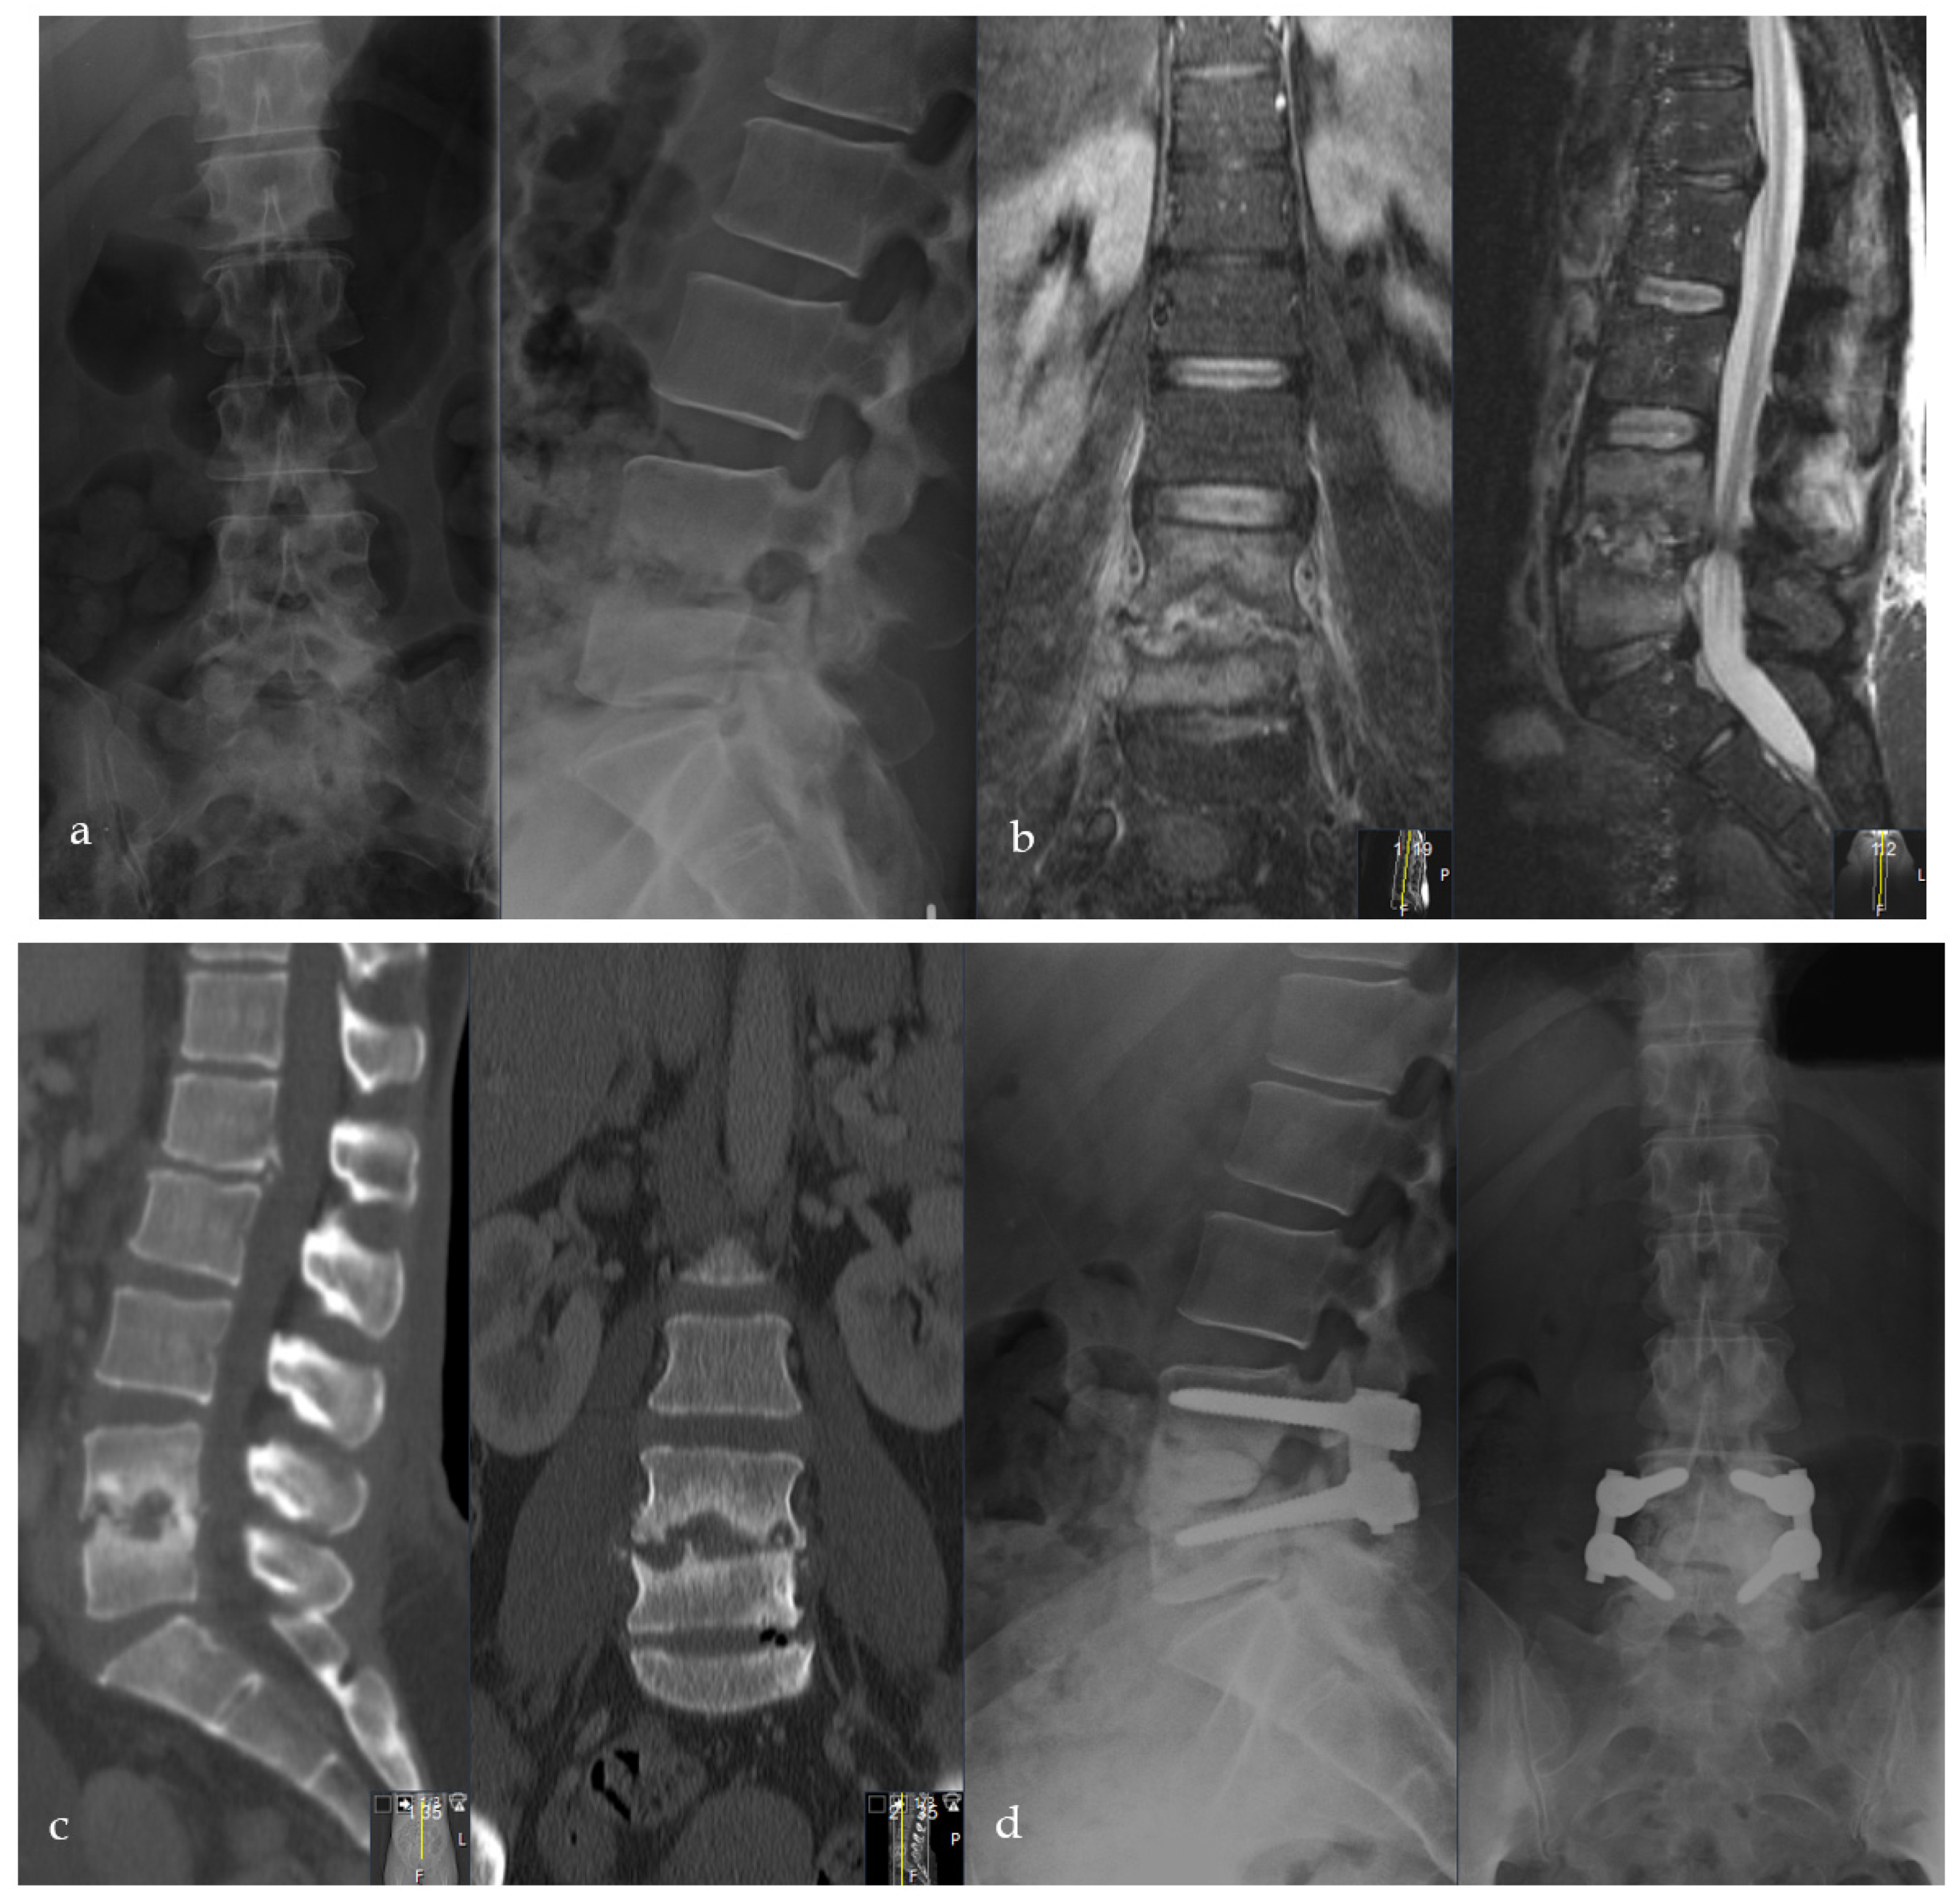

2.2. Surgical Procedure